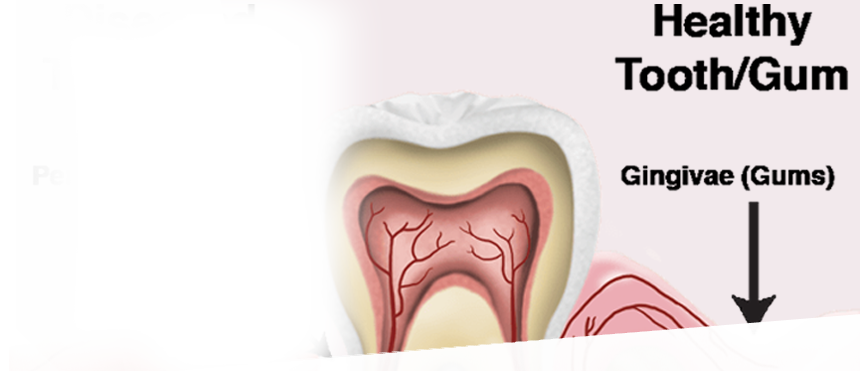

- Periodontics